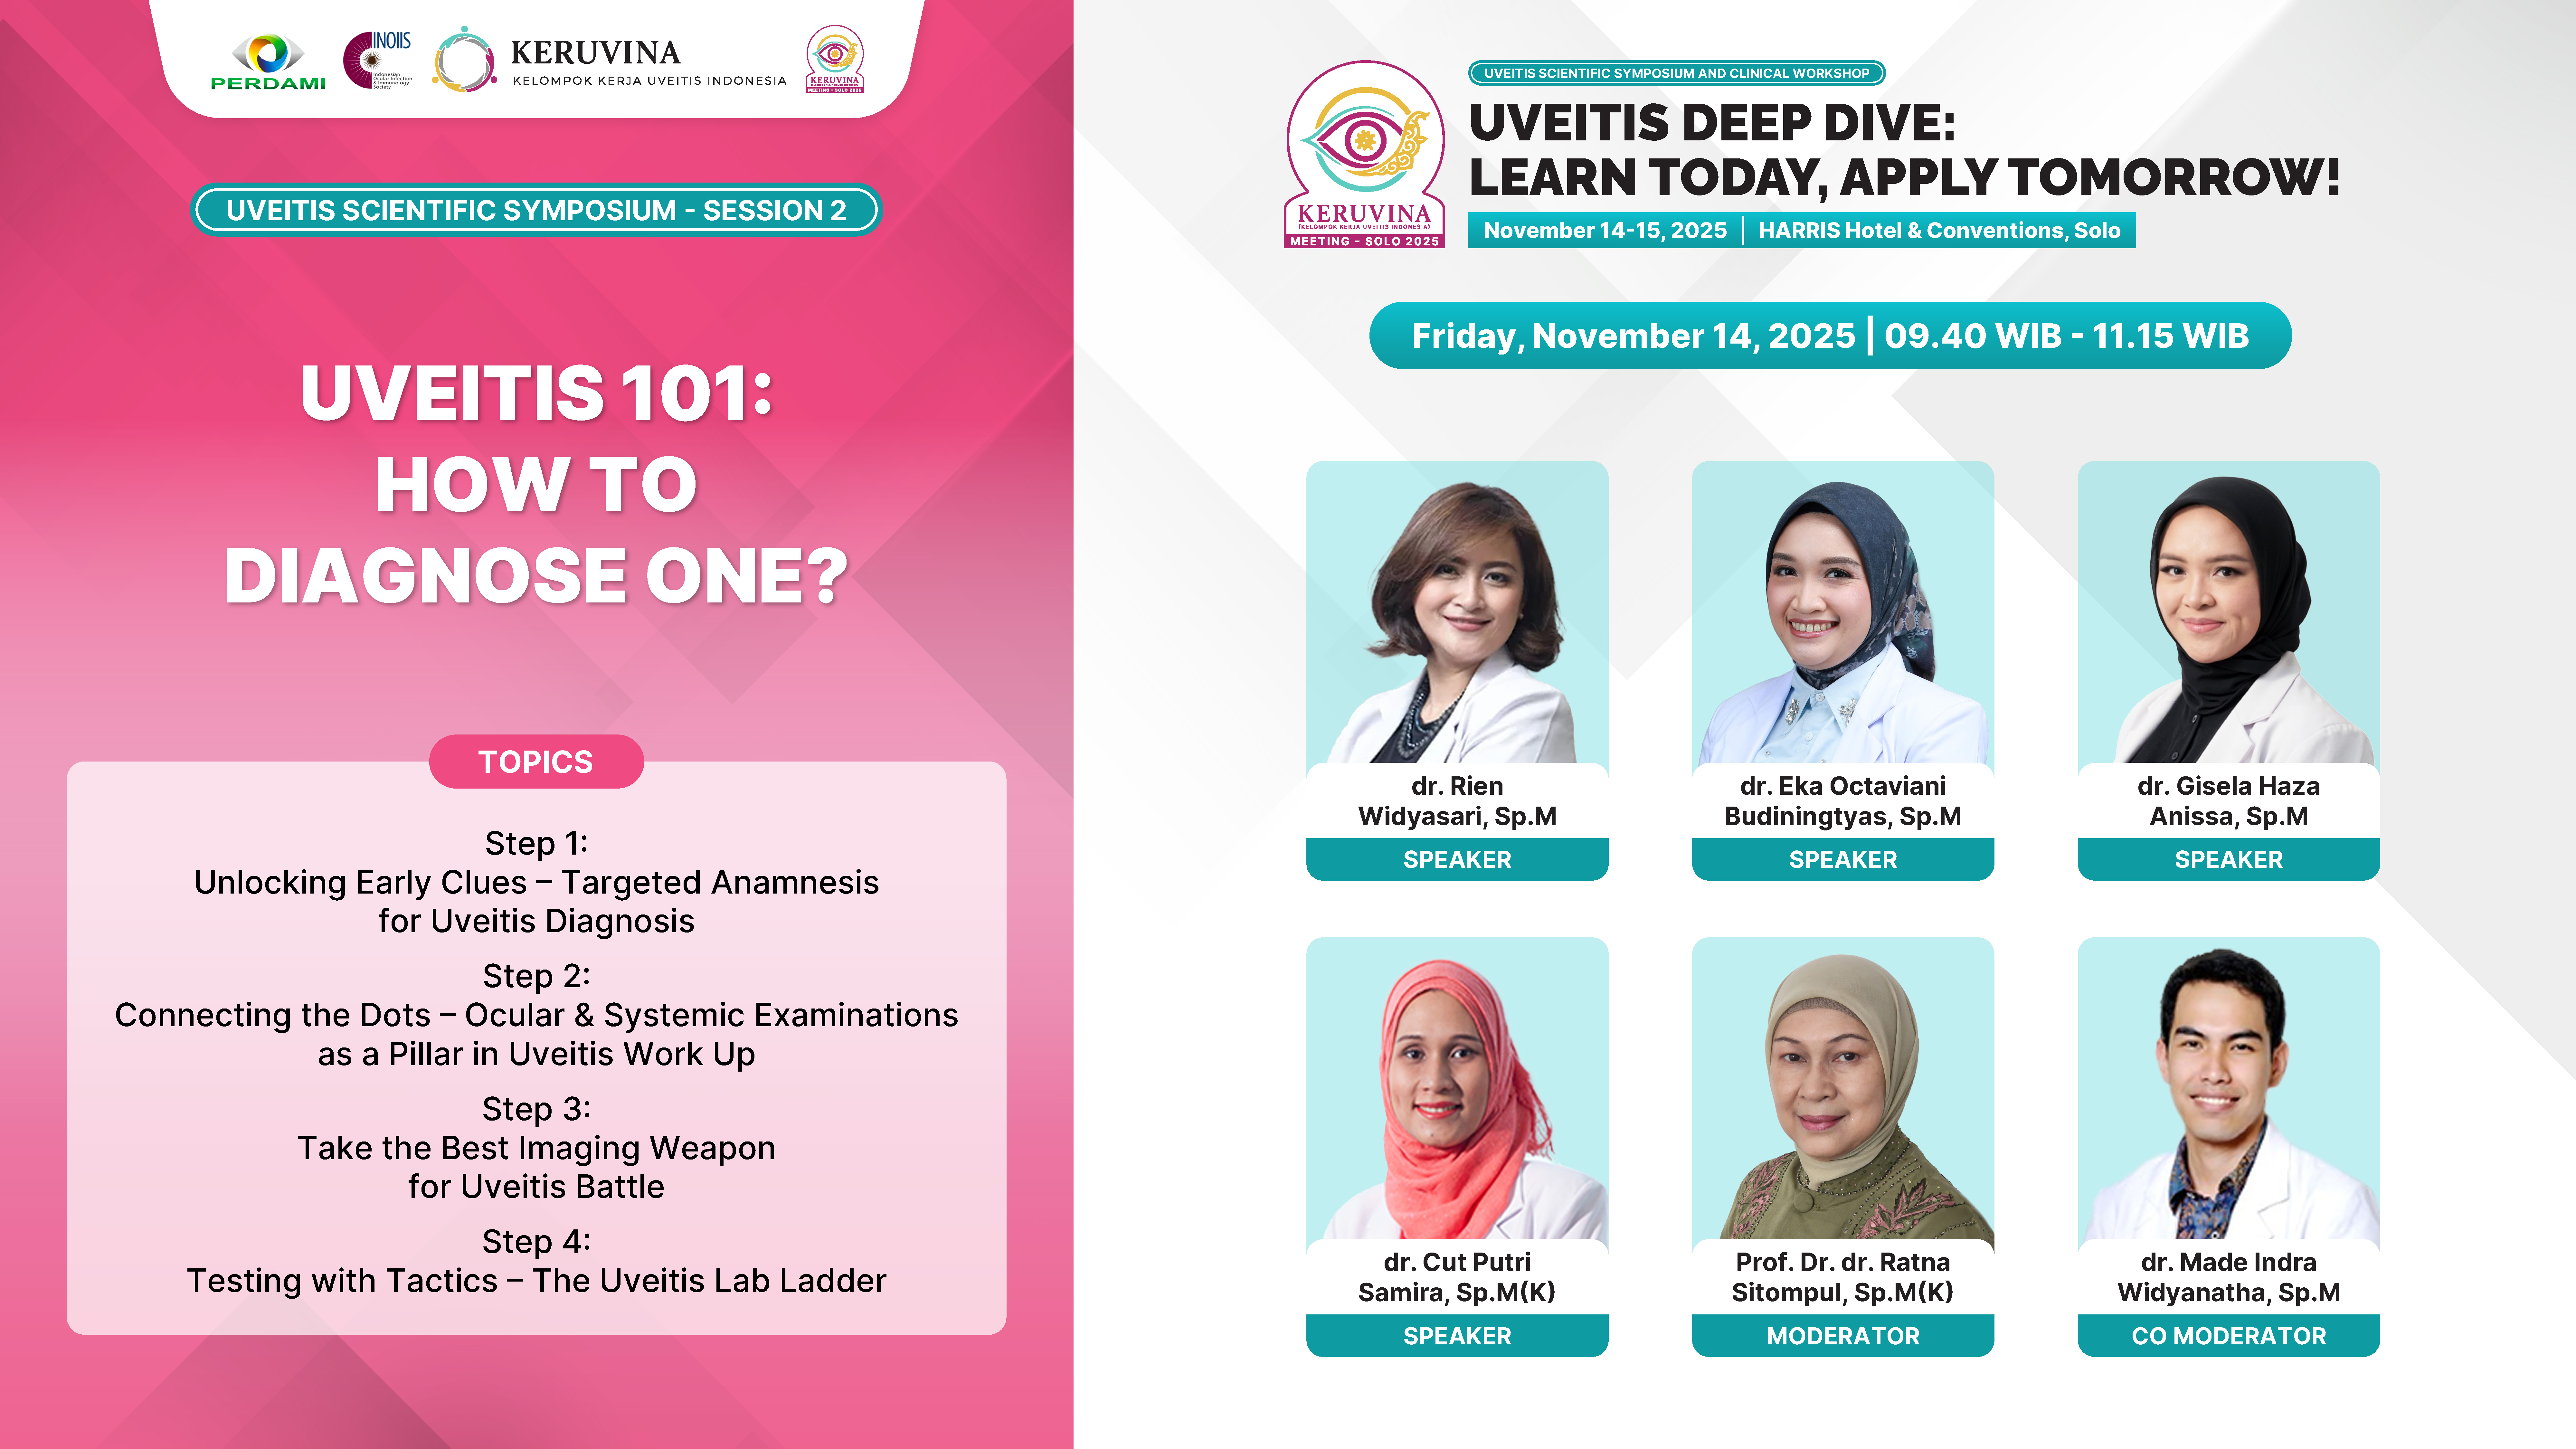

Gain practical and comprehensive updates on uveitis through the scientific symposium with expert speakers.